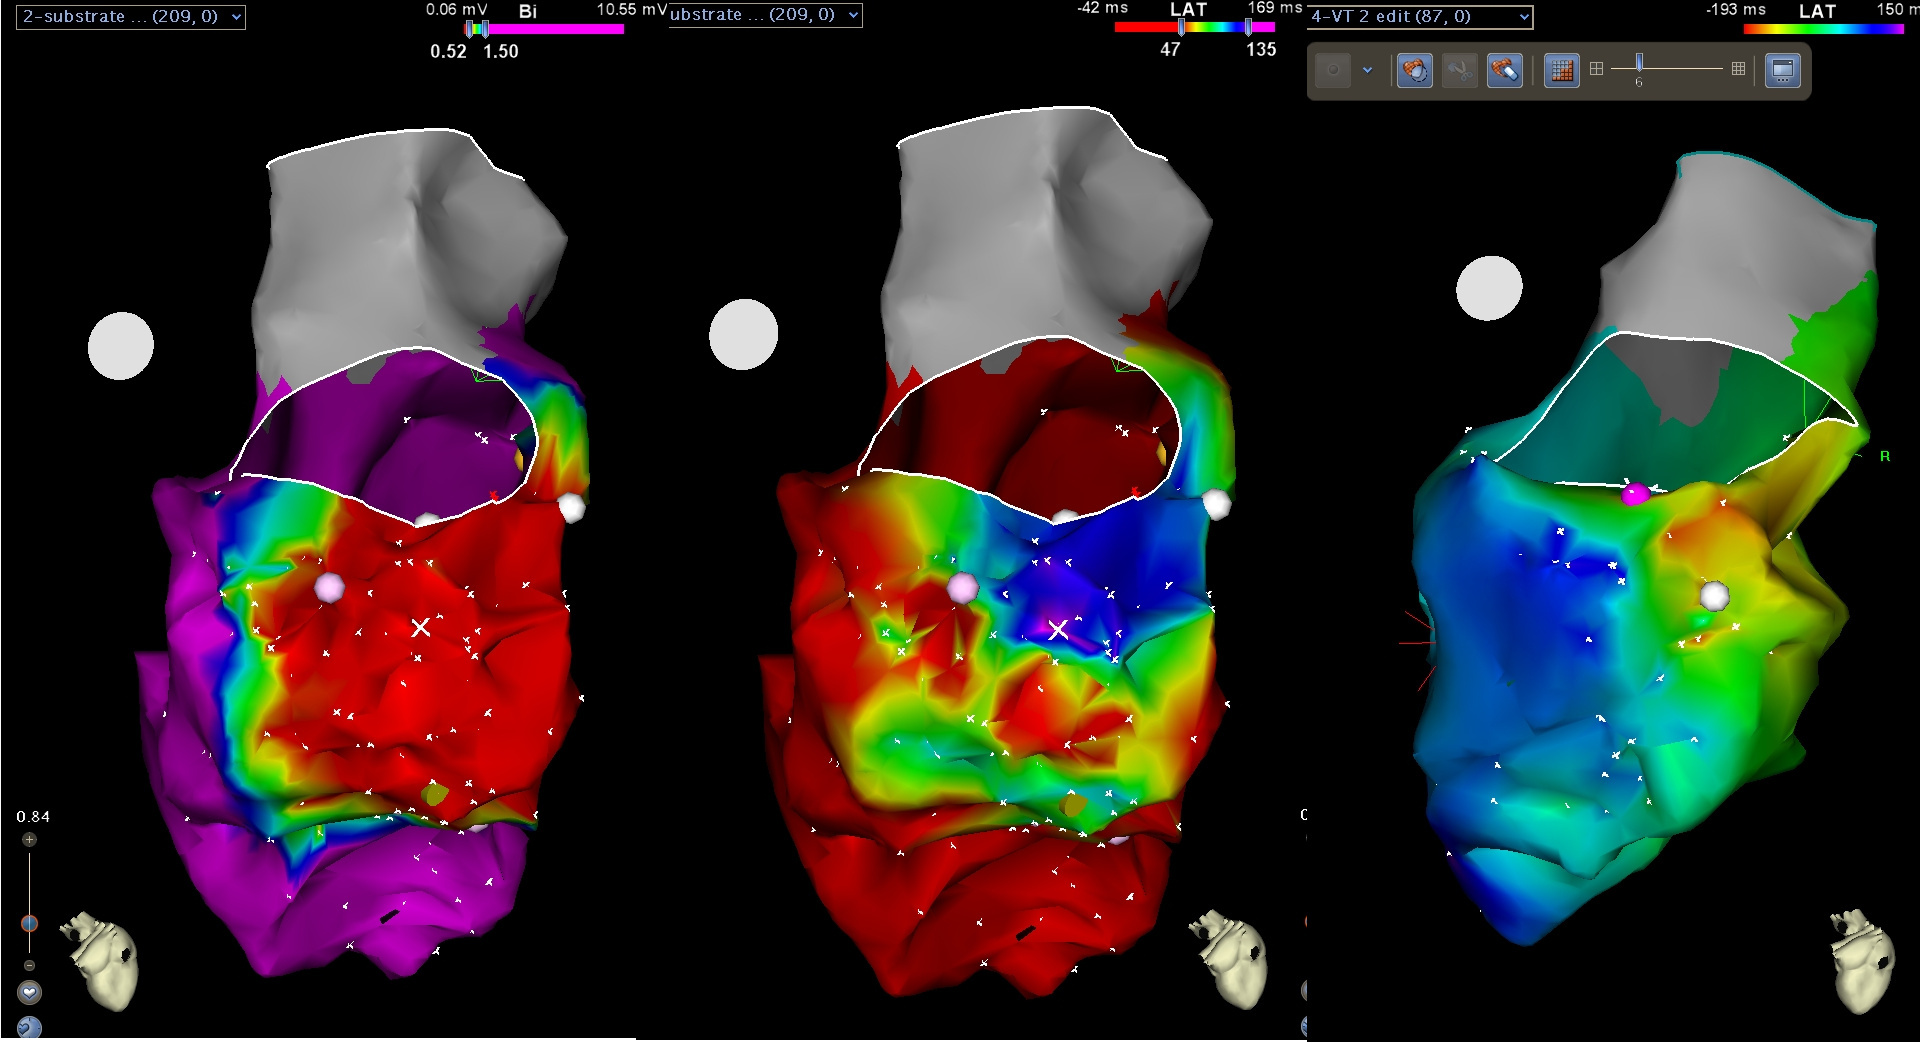

scar_channel.jpg

Substrate - Late potentials

ldp_display.jpg